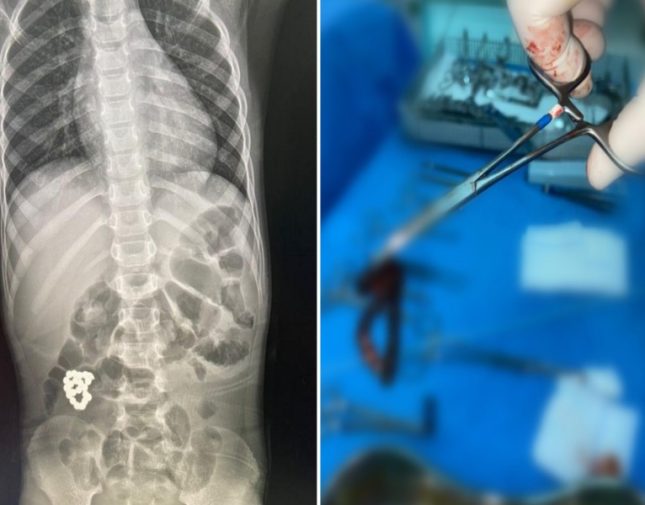

وبحسب صحيفة سبق السعودية، حضر الطفل لطوارئ المستشفى يشتكي ألماً في البطن يلازمه منذ أربعة أيام وازدادت الآلام مع الوقت،وبعد إجراء الفحوصات اللازمة، أظهرت صور الأشعة وجود جسم غريب في الأمعاء "إسوارة".

وعلى الفور تمّ إدخال الطفل لغرفة العمليات حيث قام الفريق الطبي بقيادة بروفيسور جراحة الأطفال الدكتور عمر منصور، باستخراج الجسم الغريب، وتمّ استئصال الأجزاء المتضررة من الأمعاء في عملية استغرقت ساعتين ونصفاً تكللت بالنجاح.